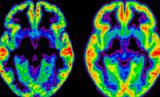

Американские ученые экспериментально доказали, что мужчины легче справляются с приступами голода, чем женщины. Исследование проводили специалисты из лаборатории Брукхавен при министерстве энергетики США: нейробиолог Джин-Джек Ванг (Gene-Jack Wang) и его помощники трижды просканировали мозг 13 женщин и 10 мужчин нормального веса с помощью позитронно-эмиссионной томографии (ПЭТ) в то время, как испытуемым предлагалась вкусная и ароматная еда. Причем на нее можно было только смотреть. Как показала томограмма, и у мужчин, и у женщин, если их «соблазнять» едой, «загораются» участки мозга, ответственные за контроль эмоций, поведения и мотивацию. Представители обоих полов, предварительно приказав себе не реагировать на пищу, впоследствии отмечали, что менее голодны, по сравнению с состоянием, когда их не просили сознательно подавлять в себе влечение к еде, пишет "Neboley". Но только у мужчин желаемое совпадало с действительным. «Хотя женщины и говорили, что не так голодны, когда пытались подавить в себе тягу поесть, их мозг, в отличие от «собратьев» по эксперименту, по-прежнему «пылал» активностью в тех местах, которые контролируют аппетит», – поясняет Ванг. По-видимому, делают вывод ученые, этим объясняется печальный факт, что женщины, как правило, чаще переедают и предпочитают заедать стресс, а также испытывают проблемы с лишним весом и страдают расстройствами пищевого поведения. Данные исследования могут помочь в создании препаратов для лечения ожирения с учетом обнаруженной «женской слабости».